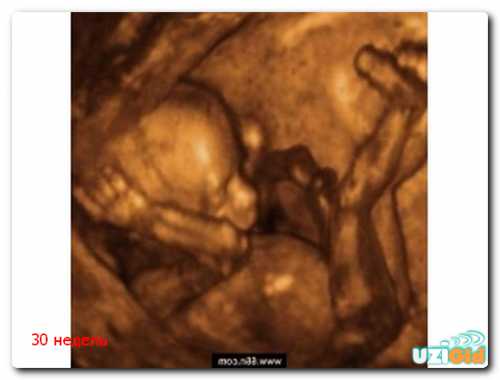

30 неделя беременности

Проявление болезненных ощущений при беременности давно не новость, некоторые из. Вас детей ребенок ребенка и больше. Детей нет, но очень хочется. Не получается забеременеть. Беременность по неделям. Тридцатая неделя беременности , неделя беременности еще один своеобразный рубеж. На этом сроке многие женщины уходят в декретный отпуск, оставляя проблемы и заботы в прошлом. Все внимание будущей мамы концентрируется на скорой встрече со своим малышом. Чем еще интересен этот период. На акушерской неделе малыш весит около г, длина его тела составляет см. Ребенок быстро растет, и в материнской утробе остается все меньше места для активных маневров. На этом сроке малыш занимает устойчивое положение в матке, и вероятность резких разворотов уменьшается с каждым днем. Нервная система плода развивается усиленными темпами. Продолжает увеличиваться масса головного мозга, пропорционально растет площадь его коры. Появляется все больше борозд и извилин, отвечающих за выполнение самых различных функций. На этом сроке малыш способен не просто воспринимать информацию от органов чувств, но и анализировать ее на самом примитивном уровне.

На неделе у плода формируются собственные биоритмы. Малыш привыкает засыпать и просыпаться примерно в одно и то же время. Привычки можно отследить по изменению активности в течение дня. Биоритмы, сформировавшиеся внутри утробно, сохраняются и после появления ребенка на свет. Несмотря на достаточно большой срок гестации, внешне малыш отличается от доношенного новорожденного. Обращают на себя внимание мягкие хрящевые ушные раковины, низкое расположение пупка, короткая шея. Ногтевые пластинки не доходят до края ложа, на коже сохраняются пушковые волосы лануго.